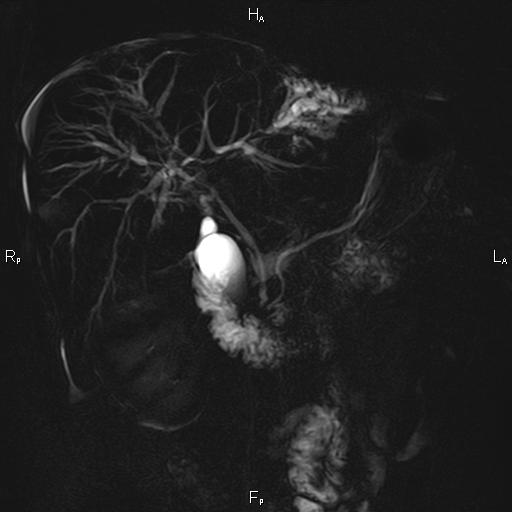

Ανώδυνος ίκτερος και παθολογικά ηπατικά ένζυμα. Ιστορικό πιθανής σκληρυντικής χολαγγειίτιδας

ΑΠΕΙΚΟΝΙΣΤΙΚΟΣ ΕΛΕΓΧΟΣ

Μαγνητική τομογραφία.

Η διάγνωση της βασίζεται στα τυπικά χολαγγειογραφικά ευρήματα κατά την μαγνητική και την ενδοσκοπική παλίνδρομη χολαγγειοπαγκρεατογραφία (MRCP-ERCP).

Οι αρχικές εξετάσεις εκλογής, όσον αφορά τον απεικονιστικό κυρίως έλεγχο, σε ασθενή προσερχόμενο στο Νοσοκομείο με αποφρακτικό ίκτερο, είναι το υπερηχογράφημα και η αξονική τομογραφία. Οι εξετάσεις αυτές έχουν αποδειχθεί ικανές να προσδώσουν έμμεσα και άμεσα στοιχεία για τη διάγνωση του χολαγγειοκαρκινώματος, όμως κυρίαρχη εξέταση για την διάγνωση του χολαγγειοκαρκινώματος είναι η μαγνητική τομογραφία (MRI, MRCP, MRA).